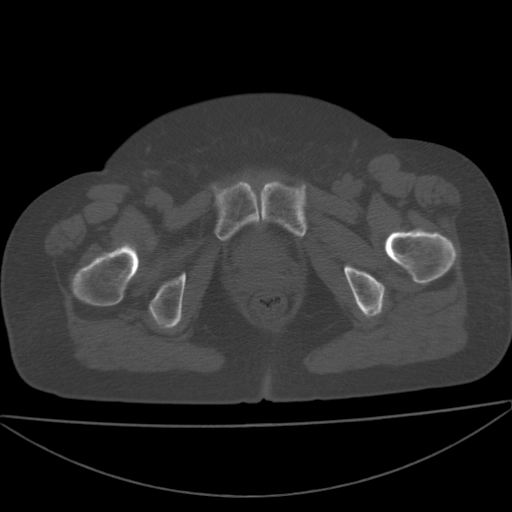

以下是引用余辉在2009-4-23 17:08:00的发言:[br]考虑右髋关节退行性变.股骨颈改变考虑陈旧性骨折可能,股骨头顶部关节面下似有透亮区,股骨头皮质环增厚,考虑有股骨头坏死

以下是引用王显瑞在2009-4-23 16:45:00的发言:[br]考虑股骨颈陈旧性骨折,股骨头缺血型坏死